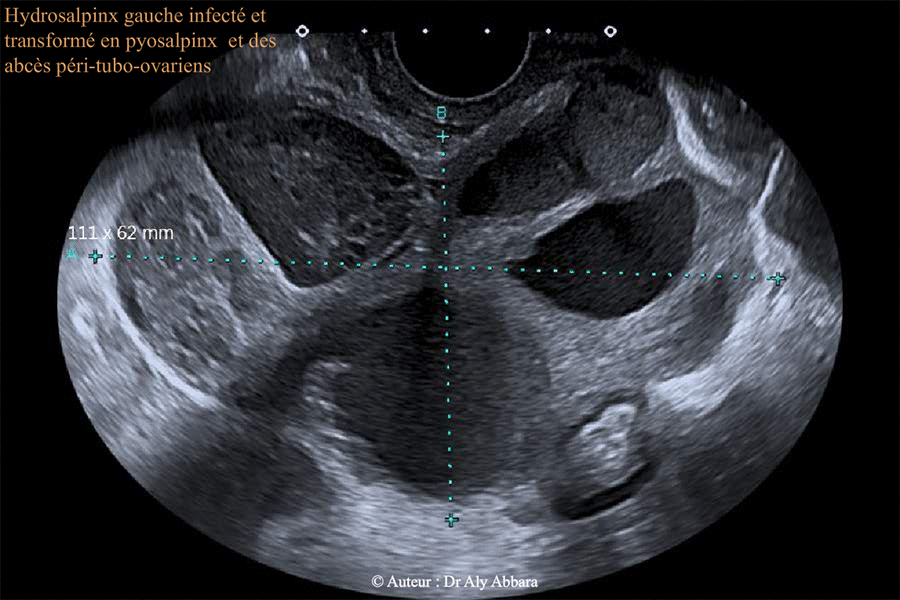

Image animée montrant l'aspect échographique d'un volumineux hydrosalpinx gauche

se compliquant d'une infection le transformant en volumineux pyosalpinx entouré par

de multiples abcès péritubo-ovariens et ovaire gauche remanié œdémateux.